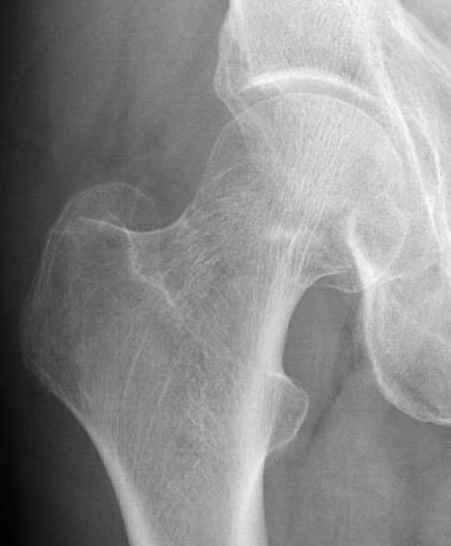

Почему неполный перелом? Я бы назвал его вколоченным!

Перелом конечно не вколоченный т.к. видно линию перелома и нет суперпозиции костной ткани.

Добрый день. Перелом коварный. Через время может произойти лизис в области "неполного" перелома и он превратиться в "полный" со всеми очевидными проблемами, тем более у пациента, склонного к питию. Если не разовьется делирий или после выхода из него, рекомендую внутренний остеосинтез винтами.

И вне контекста, еще...по классификации Devas cтрессовые переломы шейки разделяются на тензионные и компрессионные. У молодых обычно происходит по типу компрессионных переломов, они более стабильные, а у пожилых по типу тензионных (дистракционных) переломов.

Молодым дисциплинированным больным можно рекомендовать щадящее консервативное лечение на костылях. Критерием являются несмещенные переломы с обязательным частыми рентгенгенологическими наблюдениями. (См. приложенный алгоритм)

Не всегда распознаются стрессовые переломы в ранних сроках, и пациенты, продолжая нагружать конечность, в большинстве случаев обращаются, когда наступает смещение.

При боли в суставе, отдающее в коленный сустав, особенно у активных молодых, и кто занимается спортом, надо обследоваться на стрессовые переломы.

Снимок сустава с внутренней ротацией покажет абнормальную шейку, хотя золотым стандартом является Магнитно-резонансая томография.